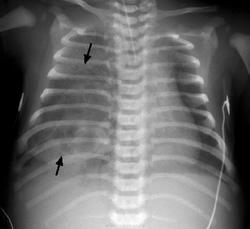

Врожденная лобарная эмфизема

• Характеризуется прогрессирующим вздутием доли, иногда – 2 долей

• В результате клапанного механизма на уровне бронхов

• 42,2% - левая верхняя доля, 35,3% - правая средняя доля, 20,7% - правая верхняя доля; по 0,9% - в каждом нижней доле

• Деструкции альвеолярных стенок не происходит

• В 50% –55% - причина неизвестна (у этих пациентов были обнаружены участки бронхомаляции или стеноза бронхиальных хрящей)

• Может быть связана с другими аномалиями (СС системы -12%-14%)

• Майерс описал три клин. типа: Iт. – кл.проявл. в младен. возрасте; IIт. – у детей более старш возраста; IIIт. – случайная находка, асимптомно.

• Респираторный дистресс - наиболее распространенный симптом

• Диагноз - рентгенография и КТ гр.полости